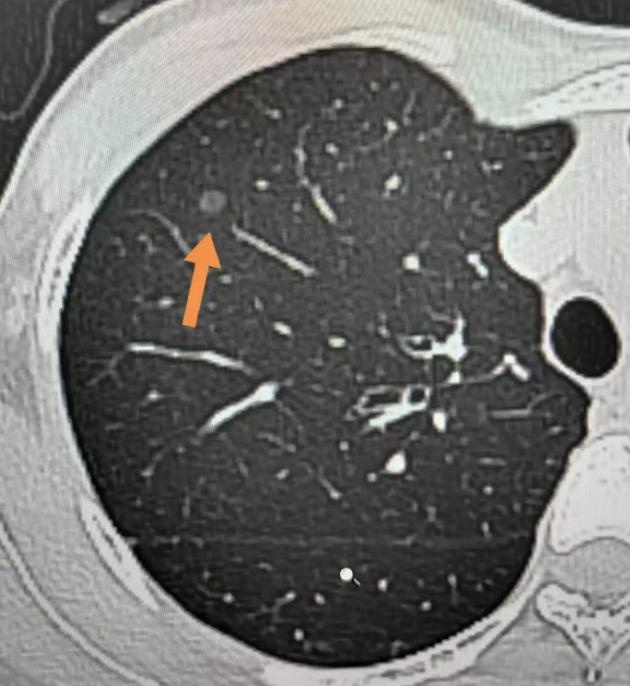

从临床统计和恶性概率角度,6mm磨玻璃结节相较于6mm实性结节通常更危险具体分析如下磨玻璃结节的危险性6mm磨玻璃结节在CT影像上呈现云雾状淡薄影,内部可能存在异常增生的细胞这种结节更可能是早期肺癌或不典型腺瘤样增生等癌前病变研究表明,磨玻璃结节发展成肺癌的比例高于实性结节,尤其是当结节。